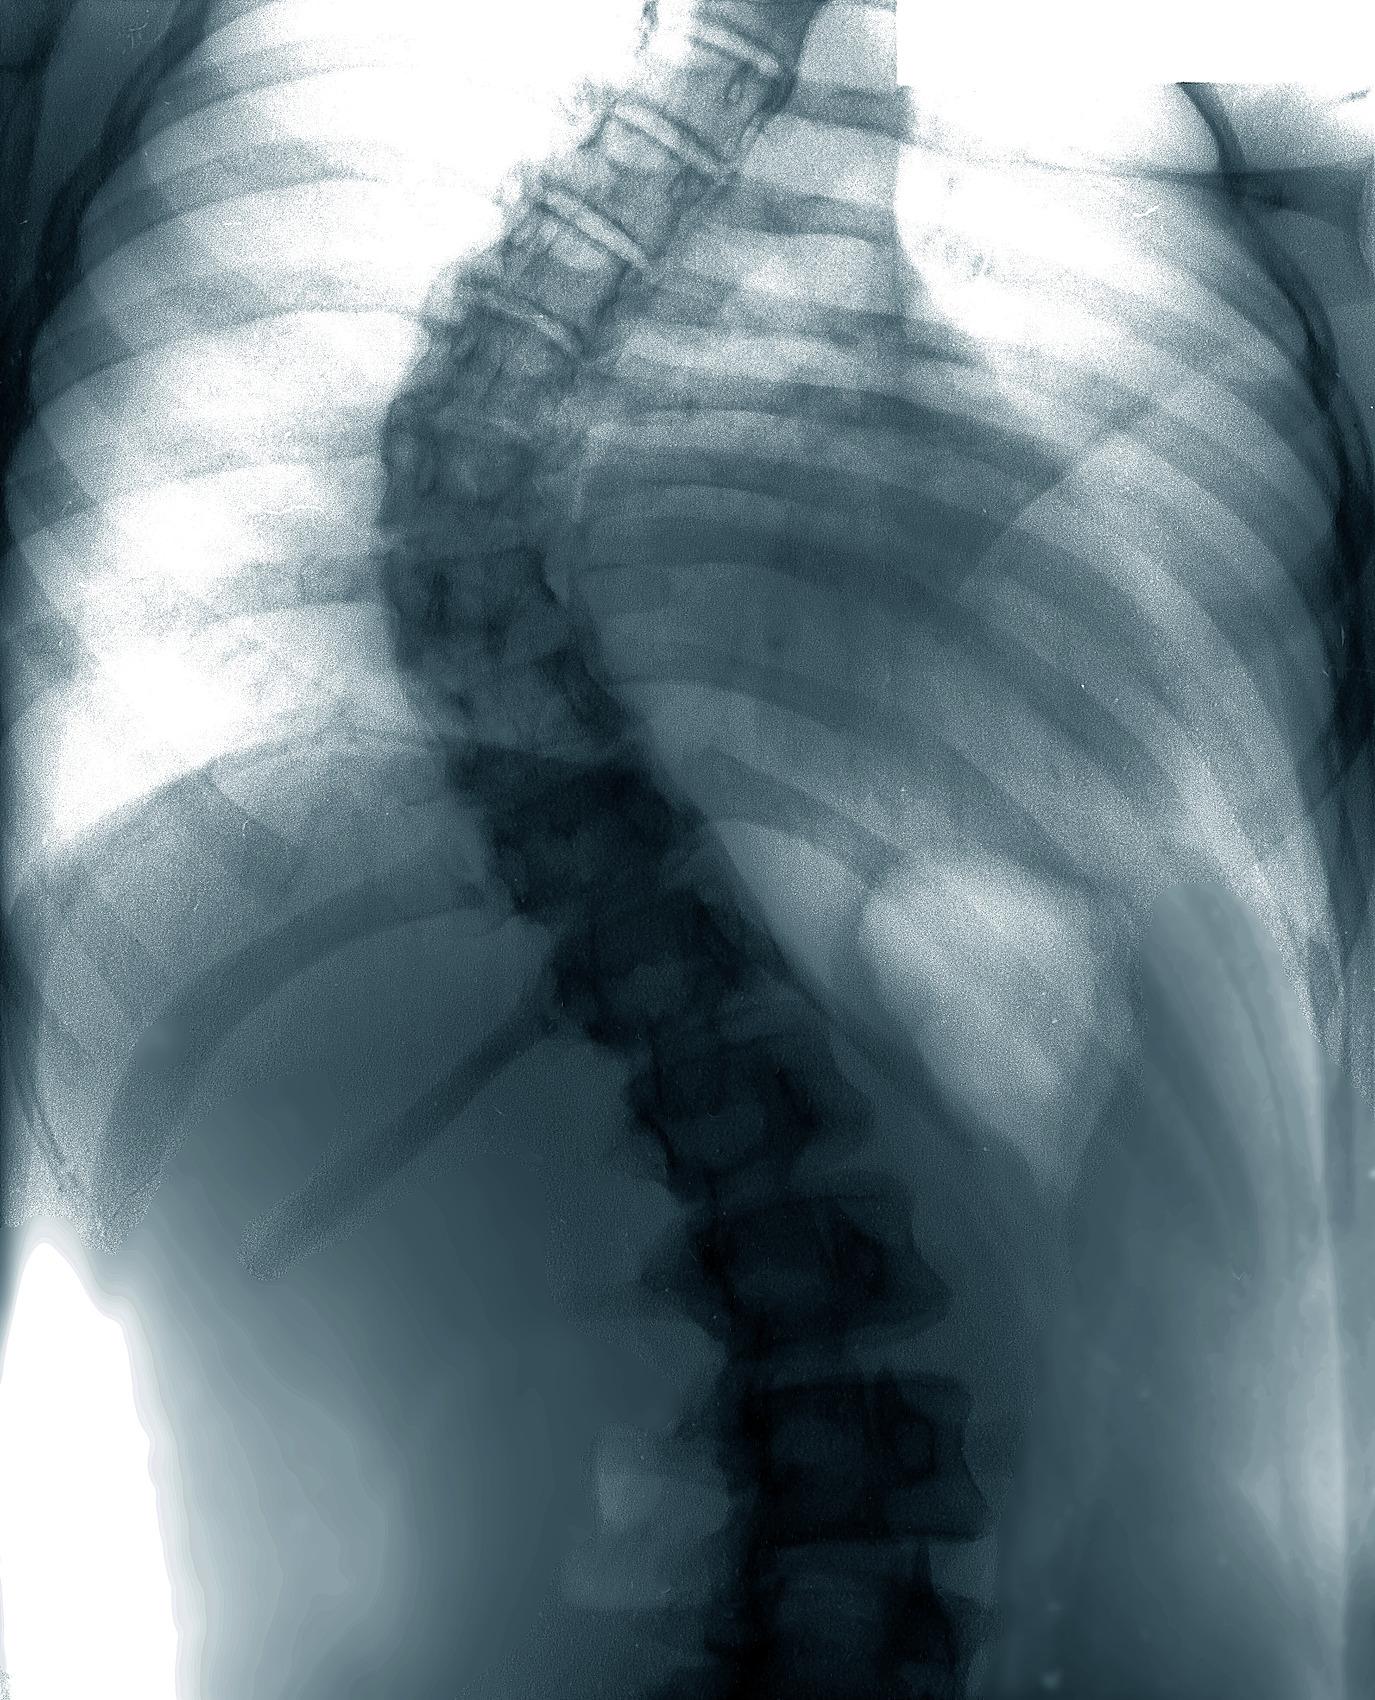

近日,于长志副教授接诊了10岁的刘同学,其家长偶然发现孩子左侧胸廓凹陷,两侧胸廓不对称,便立即带娃就医检查。经全脊柱X光检查显示,刘同学胸椎存在轻度弯曲,Cobb角(脊柱侧弯角度核心测量指标)不足10°,尚未达到临床诊断的脊柱侧弯标准。

什么是脊柱侧弯?于长志副教授解释,正常人的脊柱存在四个生理性弯曲,颈椎段凸向前、胸椎段凸向后、腰椎段凸向前、骶椎段凸向后,呈自然“S”形,支撑身体平衡。而脊柱侧弯是因先天或后天多种因素,导致脊柱失去正常曲度,单个或多个节段向侧方弯曲,常伴随椎体旋转,形成“C”形或“S”形畸形,主要分为胸弯、腰弯、胸腰双弯三种类型。

临床诊断中,医生通常以全脊柱正侧位X光片中的Cobb角为判断标准,当角度大于10°时,可确诊为脊柱侧弯。但于长志强调,青少年群体中,即便Cobb角低于10°,若脊柱侧弯仪检测旋转角大于4°,也需及时干预。